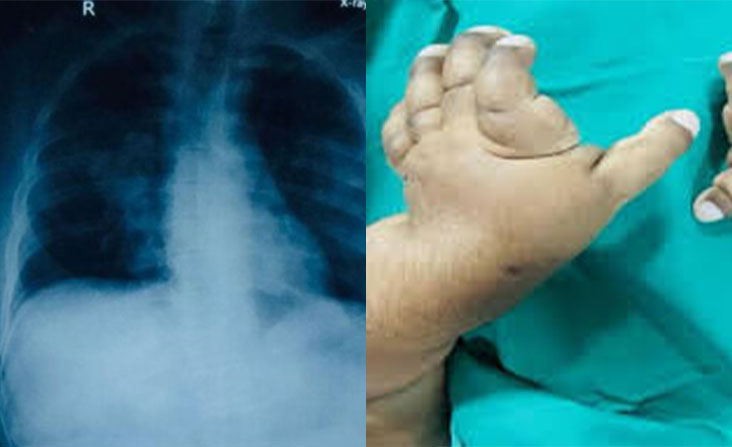

2025/1/22 Authors : Sampath Gnanarathne, Ashani Ratnayake, Gayan Kumarasiri, Avanthi Herath Welcome to WordPress. This isOsteogenesis imperfecta (OI) presents significant challenges in perioperative management due…